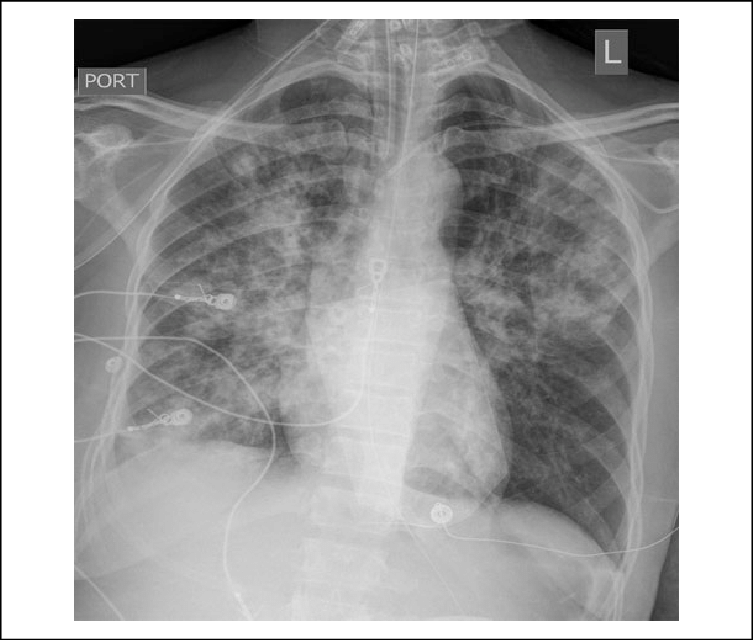

HIV+ Male with cough and SOB. Diagnosis?

What is Pneumocystis pneumonia or Pneumocystis jirovecii pneumonia?